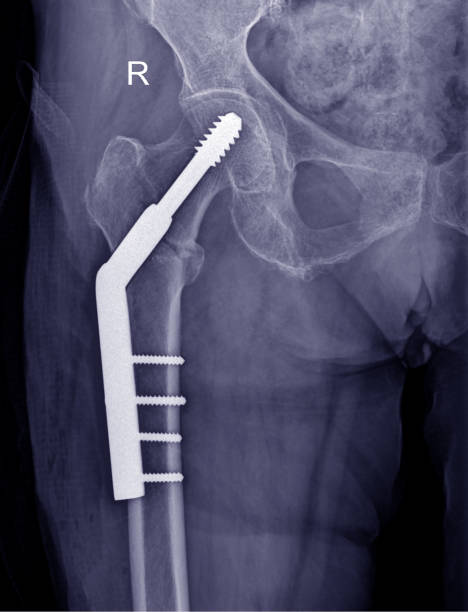

Surgical intervention with plates, screws, intramedullary nails, or external fixation devices is frequently used to treat complicated fractures. Regaining strength and mobility after surgery depends equally on post-operative therapy. Advanced surgical techniques that encourage better alignment, faster healing, and a lower risk of long-term handicap are the specialty of the Best Surgeon for Complex Fracture Fixation in Ulwe, Navi Mumbai.